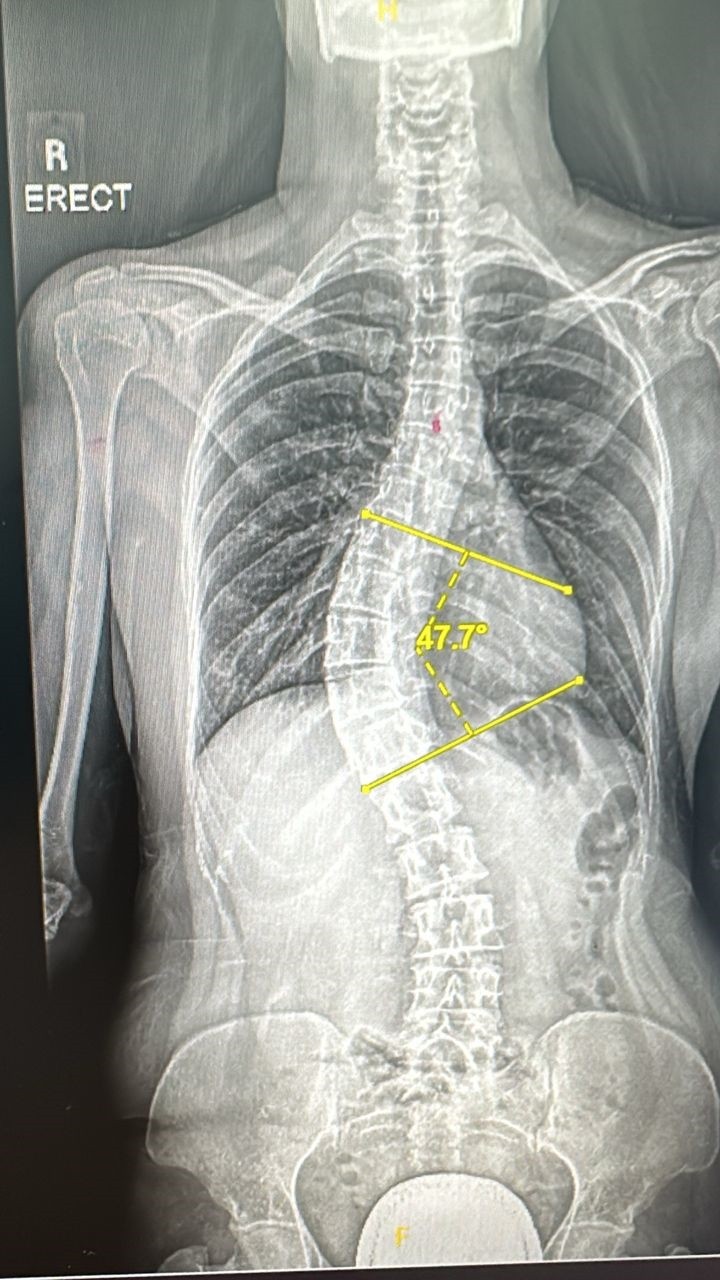

罗秀燕两侧肩膀不平,背部一侧隆起。

罗秀燕30岁时第一次因此寻医,证实脊椎侧弯47度需手术矫正,惟医药费庞大,她仅有能力负担1万5000令吉,尚缺5万5000令吉,因此向大山脚瑶池金母慈善基金(ONE HOPE CHARITY)求助。

该基金会主席拿督蔡瑞豪说,据医生告知,如果没有进行手术,脊椎料将每年侧弯一度直到生命结束,而且持续疼痛,甚至压迫内脏器官;术后不仅可避免脊椎持续侧弯不再疼痛,也可如常生活及运动。